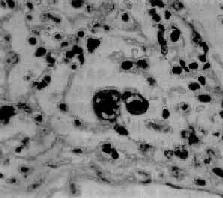

⑤病理的基本病變是纖維素性滲出,其肺淤血改變是全肺的血管擴張。

(3)痰中可查見含鐵血黃素巨噬細胞。